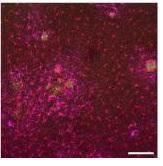

Une thérapie qui « marche » chez la souris : ainsi les cellules de cortex de souris n'ayant pas reçu la thérapie génique présentent des plaques amyloïdes (en vert), entourées par les cellules gliales (Voir visuel du haut).

· les souris ayant reçu la thérapie génique présentent très peu de plaques amyloïdes (Visuel du bas), par rapport aux souris non traitées,